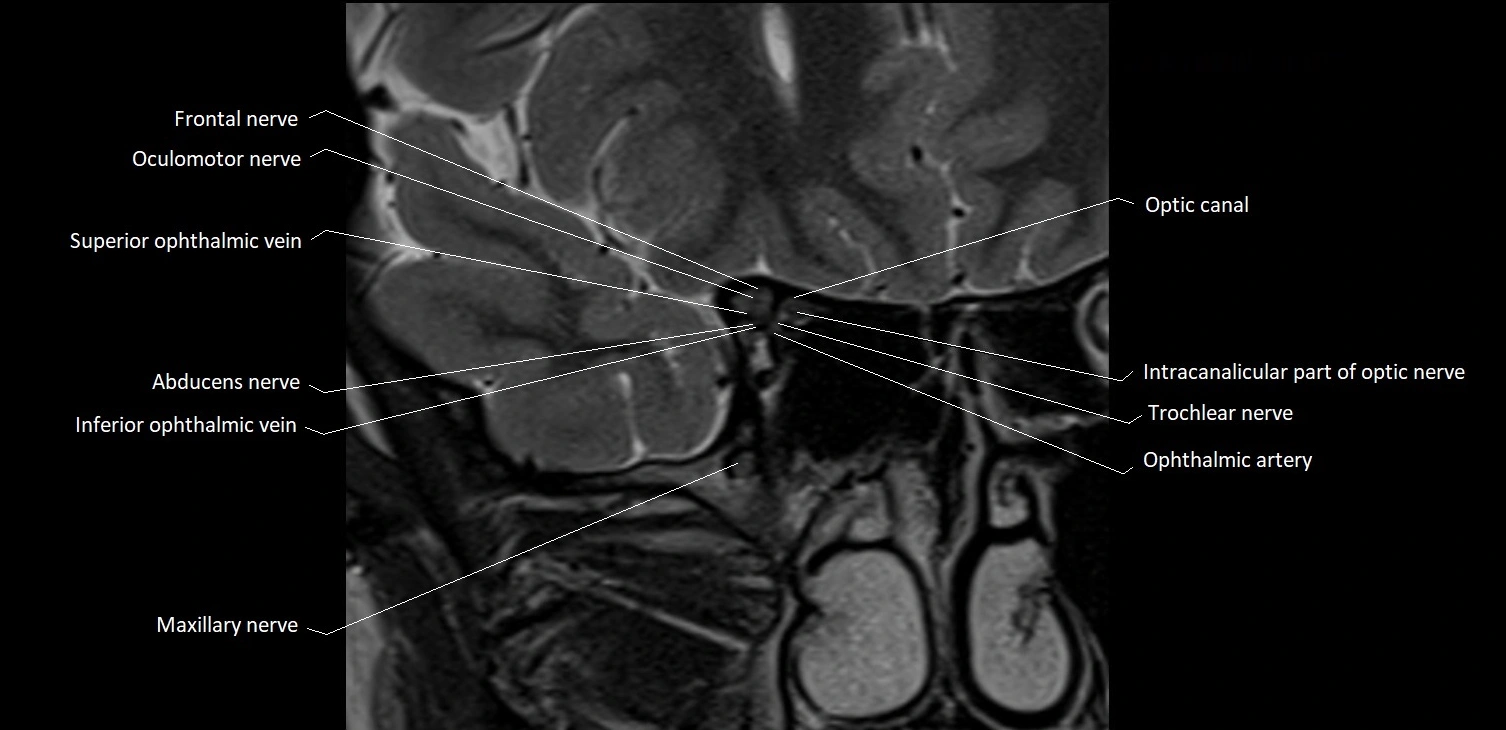

- Frontal nerve

- Oculomotor Nerve (Cranial Nerve III)

- Superior ophthalmic vein

- Abducens nerve (Cranial nerve VI)

- Inferior ophthalmic vein

- Intracanalicular part of optic nerve

- Optic canal

- Trochlear nerve (Cranial nerve IV)

- Maxillary nerve